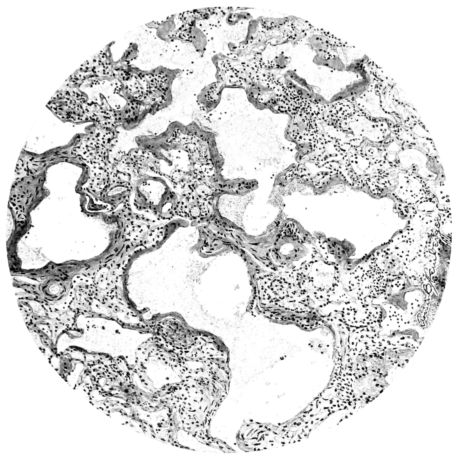

Histological Picture.

No matter what the portion of the lung from which the sections are derived, the fundamental changes found are the same. The subpleural sheets are spread wide apart, now by empty spaces, now by coagulated fluid. The process extends from the surface through the interlobular septa (Fig. XX), and is accentuated where the connective tissue is more prominent around vessels and bronchi. The nature of the infiltrate in the subpleural and interstitial tissues becomes more evident in the alveoli, which likewise are filled. The material varies somewhat in appearance, probably dependent upon its proteid content. Not infrequently the alveoli contain a homogeneous, pink-staining mass, which resembles the colloid of the thyroid gland. Again, it may be simply a coarse granular precipitate (Fig. XXIII), and in still other instances, small sticks and strands form the bulk of the alveolar content (47, 92, 140, 156). This subpleural, interstitial, perivascular, peribronchial, and alveolar edema, which is a term applicable to this collection of fluid, is very prominent, and although its intensity varies in different portions of the lung; and although it may be replaced in some areas by other types of exudate, unquestionably, this is the dominating expression of the inflammatory process in the early stage of the disease.

As might be expected from the gross appearance, the alveoli vary in size. At times slightly collapsed and at other times overdistended, their lumina are still the seat of the inflammatory exudate, although the mechanical change may allow of some variation in the appearance of their walls. As a rule, however, the alveolar wall is prominent and owes its conspicuousness to the tortuous, engorged vessels within. These vessels contain red blood cells almost exclusively, and on account of the partial, occasionally complete, loss of the lining epithelium, the alveolar wall appears as a huge, dilated arteriole (101) separating the lakes of coagulated material in the spaces (Fig. XXIII). There are areas, as indicated above, where the alveolar content may be more definitely arranged in the form of beaded or homogeneous strands of different caliber; the smallest resemble delicate threads. They tend to converge toward the alveolar wall like wheat in a sheaf, and often pass through this wall by way of the so-called pores of Cohn; as soon as the body of the neighboring alveolus is reached, they again present a fan-like expansion into innumerable, fine strands (Fig. XXII). Where the exudate is more fibrinous, the alveolar wall is less likely to be distended, its vessels are not so prominent, and their content of red blood cells is definitely decreased. Still this is not the most extreme type of alveolar exudate met with at this stage. Perhaps, the most striking, although not the most frequent, exudate has a superficial resemblance to a huge, red blood clot, and it may be difficult to make out the alveolar walls separating the masses of well preserved red blood cells that fill the alveolar spaces. These areas are indistinguishable from infarcts and may be associated with thrombotic arteritis in near-by pulmonary vessels (47) (Figs. XXIV and XXV). Among the red blood cells an occasional strand of fibrin, a desquamated alveolar epithelial cell, and rarely a polymorphonuclear leucocyte may be encountered. The alveolar wall itself varies in the definition of its outline. When its vessels are greatly distended, when its alveolar epithelium is gone, and when its content consists largely of red blood cells, it is difficult to distinguish from the exudate which it encloses. However, when it is more compressed or when its epithelial lining cells are still more or less intact, it may be seen as a blue-staining strand under the low power of the microscope, for the well preserved nuclei lend it prominence.

21There are, of course, variations in the extent of the serum, the fibrin, and the hemorrhage in the exudate of the alveoli, and while these different types may occur as pure forms, often they are associated. In still other areas and varying in prominence, one finds as characteristic an exudate, not only of serum, strands of fibrin, and red blood cells, but also a diffuse dotting of the exudate with bacteria, singly, in pairs, clumps, and chains (92, 164) (Fig. XXI). This type of reaction is uncommon in pulmonary disease. It resembles more closely a streptococcus cellulitis such as is encountered frequently in the subcutaneous tissues, for example, a woody phlegmon, or a sero-hemorrhagic exudate like the avirile response to a rapidly fatal hemolytic streptococcus serositis. A similar reaction has been reproduced experimentally in animals which have been rendered aplastic with benzol previous to pulmonary insufflation, and it is conceivable that the lack of polymorphonuclear response in the inflammatory exudate may be associated with some such general destruction or temporary suspension of leucocytic formation (160).

A more striking picture, however, even than this aplastic alveolar exudate appears in the terminal bronchioles. In many instances, these are conspicuous on account of their size, for they are dilated to form prominent, often irregular, sacs (Fig. XV). The distention of these terminal bronchioles may be so great that the surrounding alveoli are compressed. What makes them even more conspicuous is their lining, once epithelium, but now a swollen, thick, homogeneously staining material, with complete loss of architecture; the material forms (with hematoxylin and eosin) a red band limiting the lung tissue and sharply demarcating it from the exudate within the bronchioles (48, 92). However, this ribbon of red, often thickened by fibrin deposition, is not always pure, for bacteria thrive in the dead tissue. They occur singly, paired, in chains, and also as circumscribed, dense masses which in size and position, simulate nuclei (162) (Fig. XVI). This same hyalinization of the epithelium, it will be recalled, occurs in the larger bronchi (Fig. V), and there, too, bacteria frequently develop in the dead tissue (Fig. VIII). In the smallest bronchiolar ramifications, acute epithelial necrosis is not infrequently encountered, even when the surrounding lung tissue is relatively normal (Fig. XVI). That the process does not stop with the epithelium, but, as in the larger bronchi, may extend through the entire structure of the bronchioles, is manifest. Even the alveolar walls may be involved and frequently homogeneous pink or red bands, now the phantom of the former viable lung tissue, mark the presence of the old wall of the alveolus (Fig. XVII). Occasionally, some architecture remains in this pink ribbon and then the involvement seems to be primarily in the vessels of the wall. Not all the vessels are involved, and next to a hyaline thrombus in one, there may be fresh blood, usually red blood, in its neighbor. The alveolar epithelium is usually denuded and thus accentuates the intensity of the change.